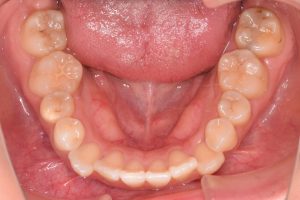

初診時(2022年12月)と装置撤去時(2025年9月)の写真です。

下あご

・下顎左右5抜歯

・下顎左右第二小臼歯抜歯

使用装置:上下顎マルチブラケット装置

アンカースクリュー

治療期間 2年5ヶ月

治療費 85.5万+税

リスク 歯肉退縮、ブラックトライアングル、歯根吸収、顎関節症状等